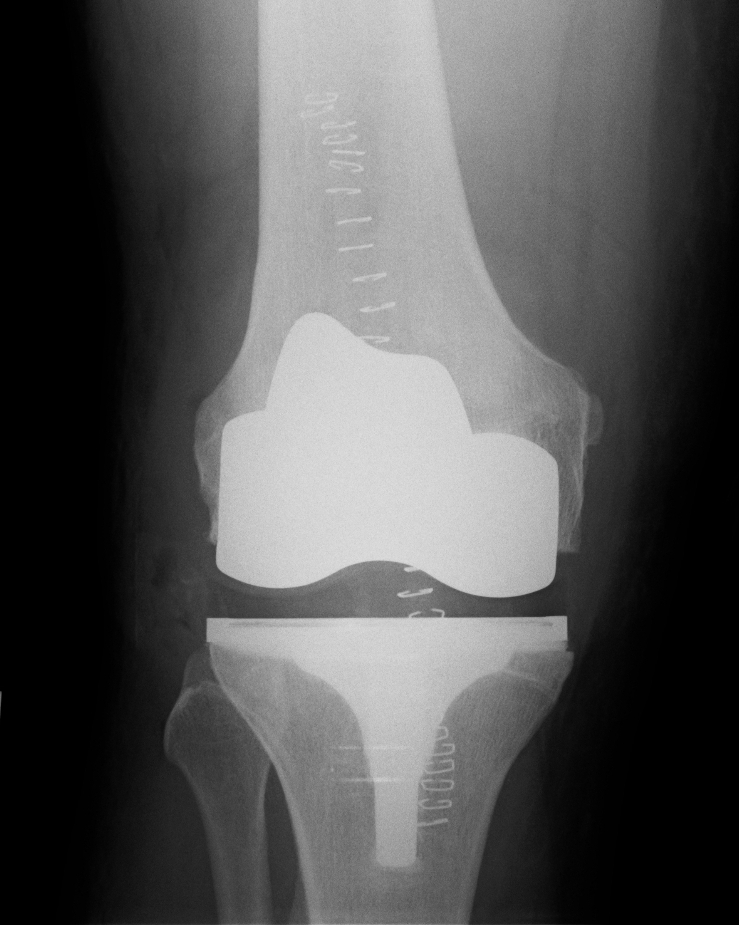

Mr Weitzel uses modern design implants that are in widespread use and have well proven excellent 10 year-survival rates of well over 95%. Patient satisfaction with the outcome has been very high and the complication rates are low. A 10-year review of Mr Weitzel’s practice showed that deep infection is extremely rare (<0.2% in knee and none in hip replacement), and there were no postoperative deaths.

Below you see X-ray examples of patients with severe osteoarthritis of the hip before (Fig 1) and after (Fig 2) total hip replacement, and of the knee before (Fig 3) and after (Fig 4) total knee replacement that have been successfully treated under Mr Weitzel’s care.